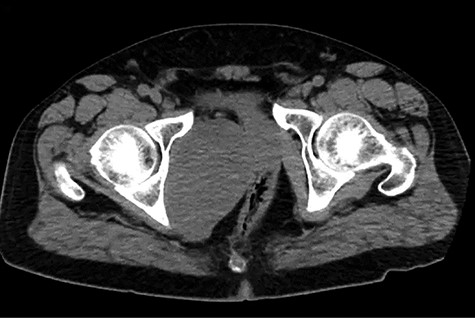

A healthy 47-year-old male with past medical history significant only for hypertension and nephrolithiasis presented to Englewood Health Medical Center in October 2019 with right flank pain radiating to the pubis, hematuria, hard stool with straining and fifteen pound weight loss over 6 months. On physical examination, multiple café au lait spots, small neurofibromas on his trunk and arms and axillary and inguinal freckling were observed. On CT scan, he was found to have a 10.1-cm soft tissue mass in the right hemipelvis and a nephroureteral stent with a 3-mm stone in the proximal right ureter (Fig. 1). Further history revealed the patient had a known pelvic mass discovered on CT approximately 10 years prior (Fig. 2), which was again observed on CT in June 2019 during a hospitalization for nephrolithiasis at Hackensack University Medical Center (Fig. 3); he had been lost to follow-up.

EHMC 10/21/19: 10.0 × 6.5 × 7.5-cm-sized right pelvic wall soft tissue mass.